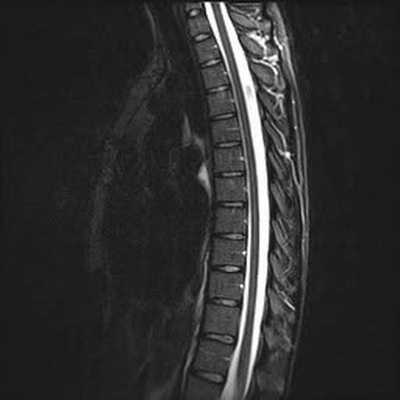

МРТ грудного отдела позвоночника что показывает

МРТ грудного отдела позвоночника в коронарной проекции

Магнитно-резонансная томография используется в дифференциальной диагностике заболеваний грудного отдела позвоночного столба в тех случаях, когда другие методы оказались малоэффективными. Данный вид аппаратного исследования безопасен для здоровья человека, не несет лучевой нагрузки и не требует хирургических манипуляций. Окончательная постановка диагноза во многом зависит от того, что показывает МРТ грудного отдела позвоночника.

В результате томографии врач получает серию послойных изображений спины, выполненных в аксиальной, сагиттальной и фронтальной проекциях. На основании полученных фото возможно построение 3D-модели изучаемой зоны.

МРТ снимок грудного отдела позвоночника в сагиттальной проекции, Т1 взвешенное изображение

МРТ грудного отдела позвоночника в аксиальной проекции

МРТ грудного отдела в сагиттальной проекции, линии разделяют позвонки Th1-12